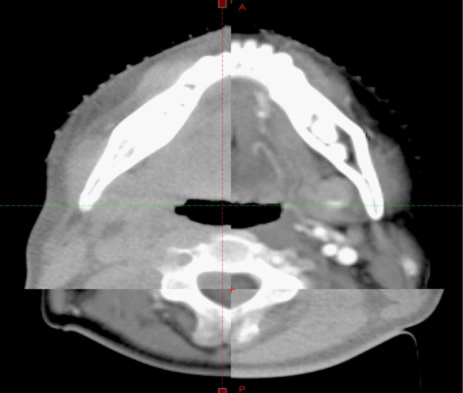

图像引导放射治疗(Image Guided Radiation Therapy, IGRT):图像引导放射治疗(IGRT)是一种四维的放射治疗技术,它在三维放疗技术的基础上加入了时间因数的概念,充分考虑了解剖组织在治疗过程中的运动和分次治疗间的位移误差,如呼吸和蠕动运动、日常摆位误差、靶区收缩等引起放疗剂量分布的变化和对治疗计划的影响等方面的情况,在患者进行治疗前、治疗中利用各种先进的影像设备对肿瘤及正常器官进行实时的监控,并能根据器官位置的变化调整治 疗条件使照射野紧紧“追随”靶区,使之能做到真正意义上的精确治疗。